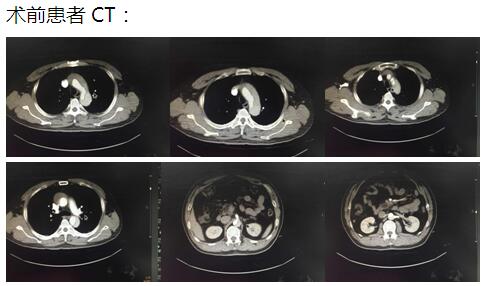

患者是一位48歲中年男性,因胸痛1小時(shí)入院,我院CT提示主動(dòng)脈夾層累及胸、腹主動(dòng)脈全層,診斷為主動(dòng)脈夾層(D ebaKey I型)?;颊卟∏槲V?,手術(shù)治療是挽救其生命的唯一希望。為了挽救病人生命,經(jīng)過(guò)麻醉科、手術(shù)室、體外循環(huán)組的術(shù)前充分討論,心胸外科廖金文主任、廖承輝副主任帶領(lǐng)團(tuán)隊(duì)決定為其施行復(fù)雜而高難度的淺低溫停循環(huán)下“孫氏手術(shù)”。術(shù)中見主動(dòng)脈全程及三分支受累,右冠受累,冠脈開口受壓狹窄,予以行“升主動(dòng)脈 主動(dòng)脈弓置換 降主動(dòng)脈術(shù)中支架置入術(shù)”,團(tuán)隊(duì)成員歷經(jīng)約10個(gè)小時(shí)的奮戰(zhàn),手術(shù)順利完成。術(shù)后六小時(shí)患者意識(shí)完全清醒,現(xiàn)在已完全康復(fù)。